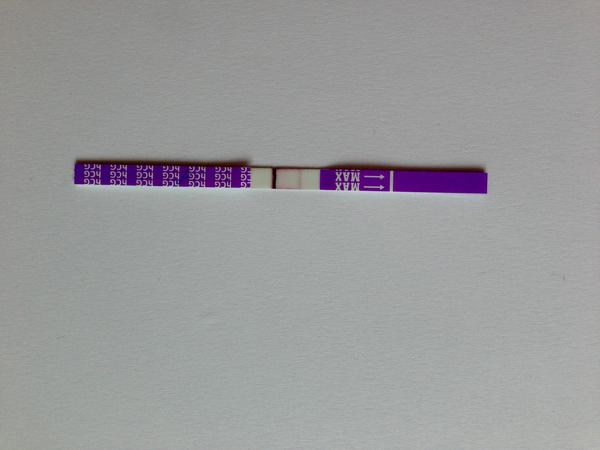

Udělal jsem radši ještě jeden - jmenuje se ForYou... Tam se objevil slabý duch, ale až tak za 3minuty! Šla jsem ven se psi a když jsem se vrátila, tak duch byl silnější...no ale to bylo skoro po půl hodině!

Tak nevim ... ☹ Dávám fotku, skuste posoudit...

- Slabá druhá čárka na domácím těhotenském testu může znamenat velmi časné těhotenství, biochemické těhotenství nebo vliv ředění moči a různou citlivost testů; spolehlivější potvrzení poskytne opakované testování z první ranní moči a krevní odběr hCG.

- V diskuzi byly zmíněny konkrétní citlivosti testů (ClearBlue 25 mIU/ml, ForYou 20 mIU/ml, RapidClear 10 mIU/ml) a zároveň varování, že intenzita čárky závisí na značce, množství barviva v testu a koncentraci moči, takže srovnávání čárek mezi různými testy je nespolehlivé.

A: Intenzita čárky závisí na koncentraci moči (nejkoncentrovanější je ranní moč), na množství barviva v konkrétním testu a na množství hCG v krvi; v diskuzi také zaznělo, že čárka může být slabá v časném těhotenství nebo při biochemickém těhotenství.

A: Několik příspěvků varovalo, že čtení výsledků mimo doporučený čas může ukázat „ducha“ vlivem zaschnutí nebo chemických reakcí; spolehlivý výsledek je ten uvedený v návodu testu v doporučeném časovém okně.

- Význam velmi slabé čárky: část diskuzí považovala slabou čárku za znamení časného těhotenství, jiní upozorňovali na možnost biochemického těhotenství nebo technické artefakty.